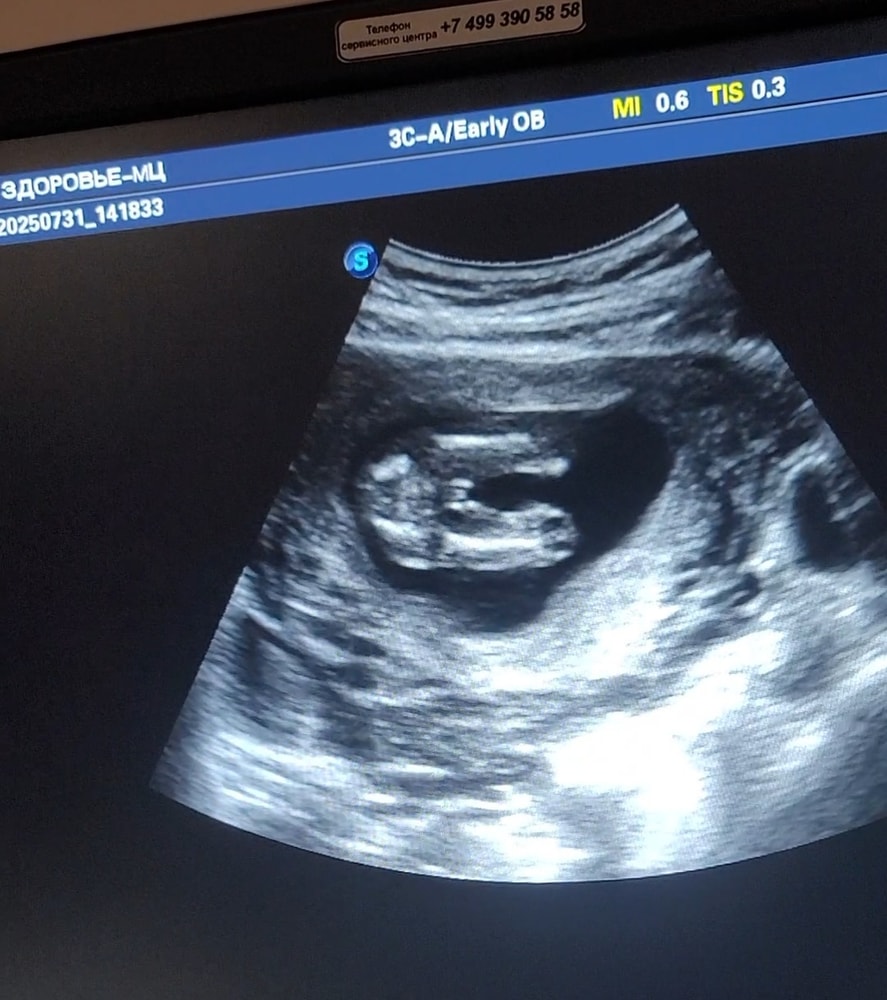

УЗИ, КТГ, доплерПоказала значит я фотки с узи своим подружкам мол ждем мальчика,а они мне начали говорить,что похоже на девочку больше.Либо с беременностью я стала более внушаемой,но теперь сомневаться начала и мой беременный мозг уже сносит🥲Врач четко показала на узи между ног,что есть 🔔🔔 и я четко видела.Еще раз приложу фотки узи,обвела что врач имела ввиду.Это ракурс как раз между ножек.Сказала у девочки не может так за контуры тела выходить.Короче,девочки кто разбирается в узи успокойте меня и мое любопытство.Хотели уже родных собирать пока тепло сообщать о внуке,а теперь во мне сомнение затесалось.Ну мальчик же,нет?Умоляю,не пишите про сдачу крови только.Если бы я знала,что так долго надо будет ждать и терпеть,то сдала бы уже на 10 неделе и не мучилась(

А у вас мальчишка)